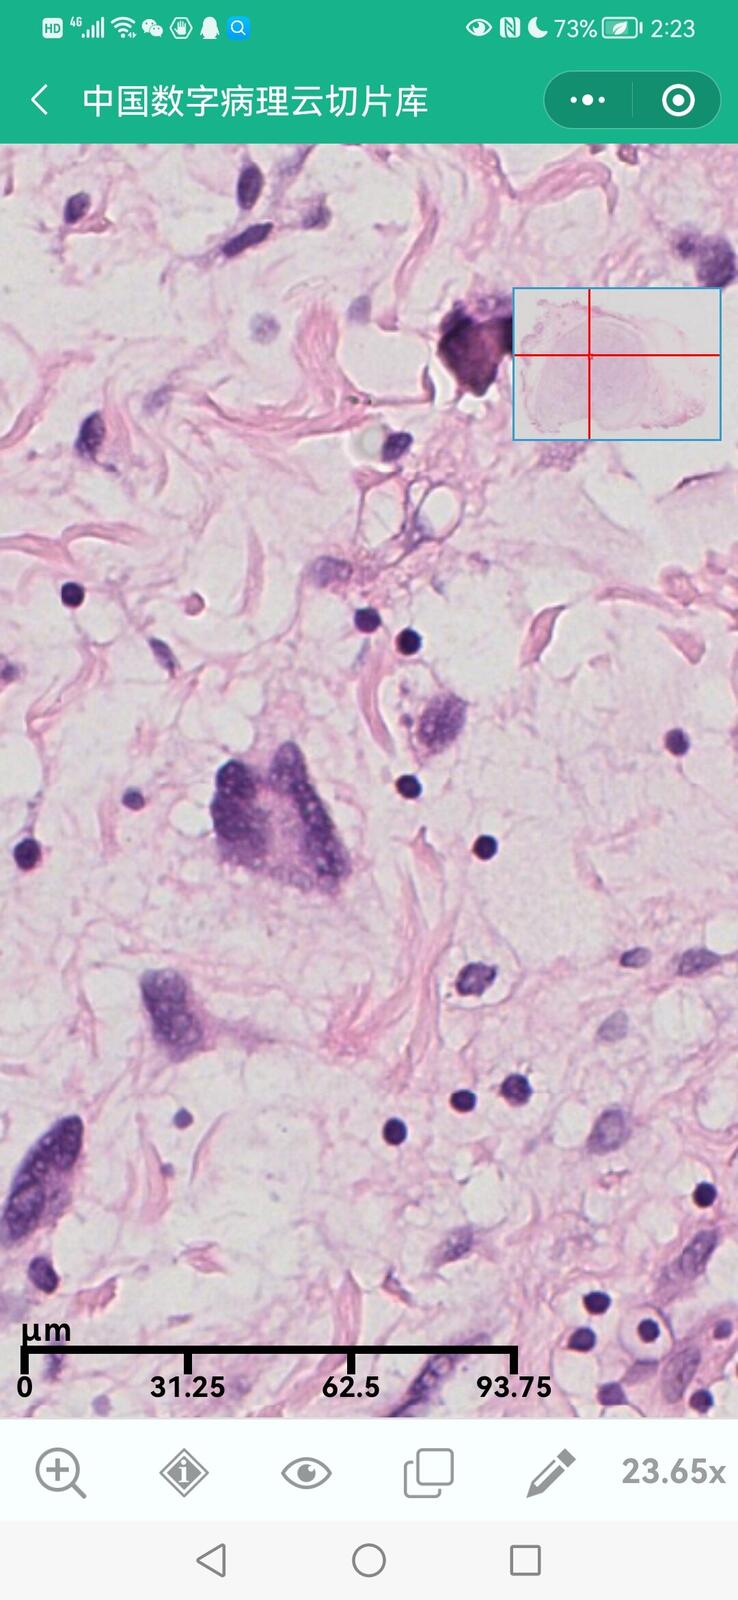

乳腺黏液性囊腺瘤伴导管内癌

乳腺多形性脂肪肉瘤

乳腺叶状囊肉瘤

乳腺分泌性癌(29岁)